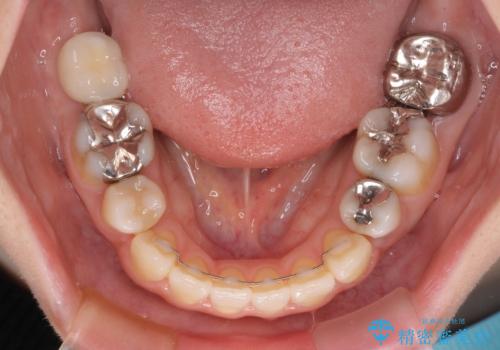

出っ歯と奥歯の欠損 ワイヤー矯正とインプラント治療

- 口元の突出感と奥歯の欠損を気にして来院された患者様です。

口元の突出感改善には、上下左右の第一小臼歯4本を抜歯し、奥歯の欠損部には矯正治療の途中でインプランを埋入していくこととしました。

矯正治療の後半にインプラント埋入を行うことで、トータルの治療期間を短縮することができました。